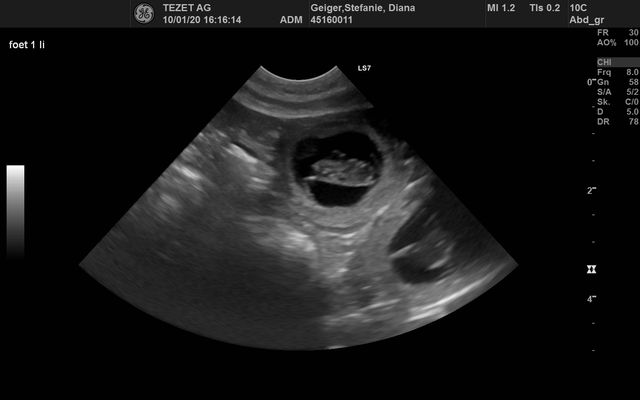

Ultraschall Diana

Wir waren beim Ultraschall